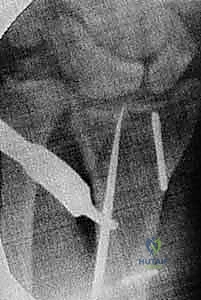

Dorsal Extra-articular Distal Radius Osteotomy: Corticocancellous Graft ### Exposure Make a longitudinal incision centered over the tubercle of Lister, in line with the third metacarpal ( TECH FIG 1A). Elevate skin flaps, taking care to protect the branches of the superficial radial nerve in the radial skin fla Incise the retinaculum over the third extensor compartment. Remove the tendon of the extensor pollicis longus (EPL) and transpose it radialward ( TECH FIG 1B). The EPL tendon will be left in the subcutaneous tissues at the completion of the procedure. Elevate the fourth dorsal compartment and its tendons subperiosteally. Preserve the integrity of this compartment. It is usually not possible to elevate the second dorsal compartment subperiosteally, so simply retract the extensor carpi radialis brevis and longus tendons radialward after opening the compartment. ### Osteotomy and Realignment Kirschner wires drilled parallel to the articular surface can facilitate monitoring of realignment ( TECH FIG 2A).

### TECH FIG 2 • A. Kirschner wires are placed parallel to the articular surface. Fluoroscopic image showing pin placement. B. The osteotomy is made with a saw as close as possible to the original fracture site. C. Lateral fluoroscopic image showing use of a lamina spreader to realign the distal fragment. D. The osteotomy has been opened and is ready for graft placement. (Copyright Diego Fernandez, MD, PhD.) A distractor or small external fixator may facilitate realignment and provisionally stabilize the fracture. The proximal threaded pin is drilled into the radial diaphysis perpendicularly in a position that will not interfere with implant application. The distal threaded pin is drilled at an angle equal to the desired correction of the lateral tilt of the distal radius articular surface so that distraction of the two pins will bring this pin parallel to the proximal pin (perpendicular to the radius), thereby restoring alignment. The pins should be drilled so that they also help restore the appropriate ulnarward inclination of the distal radius articular surface when distracted. Planned angular corrections can be monitored with sterile geometric templates. The osteotomy is made parallel with the distal Kirschner wire and as close to the original fracture site as possible using an oscillating saw ( TECH FIG 2B). If the fracture is not yet completely healed (nascent malunion— usually within 4 months of injury), recreate the original fracture line by carefully removing fracture callus at the fracture site. This callus can be saved and used as bone graft. If the fracture is solidly healed, attempt to identify the prior fracture site. If this is uncertain, choose a site that creates a distal fragment large enough to facilitate manipulation and internal fixation while trying to stay distal enough to take advantage of the healing capacity of metaphyseal bone. A lamina spreader can be used to help realign the distal fragment as well ( TECH FIG 2C,D). Care must be taken when operating on osteoporotic bone. Additional provisional stability can be provided by placing 1.6-mm smooth Kirschner wires. If the ulnar variance can be restored with angular realignment alone, the volar cortex can be cracked and hinged open in an attempt to maintain some stability of the osteotomy. If lengthening of the volar cortex is required to restore ulnar variance, a second distractor in another plane (eg, direct radial) may prove useful for obtaining and maintaining alignment. ### Graft Insertion and Fixation Once the osteotomy is created and the radius realigned, bone graft is inserted. Harvest bone graft ( TECH FIG 3A). Either a corticocancellous (structural) bone graft or cancellous bone graft can be used. Potential advantages of a structural graft include immediate structural support ( TECH FIG 3B) and the possibility of using a smaller implant and thereby avoiding tendon irritation. A cancellous (nonstructural) bone graft can be harvested using trephines ( TECH FIG 3C). This avoids tedious, difficult, and unpredictable harvest and contouring of corticocancellous grafts as well as the morbidity associated with harvest of a standard iliac crest bone graft. Apply a single T- or Pi-shaped plate or two 2.0- or 2.4-mm plates (one applied dorsally, ulnar to the tubercle of Lister, and 147 the other applied radially between the first and second dorsal compartments).